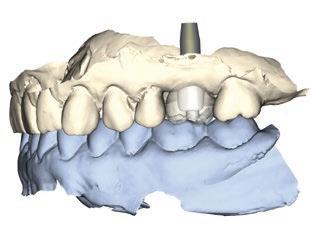

L’émergence des scanneurs intra-oraux a transformé la pratique dentaire moderne, en ouvrant la voie à des approches numériques simples, précises et accessibles. L’implantologie bénéficie pleinement de ces avancées, permettant une planification plus rigoureuse et une exécution prothétique optimisée.

Ce module vous propose de structurer et d’intégrer l’implantologie dans un flux numérique complet, de la planification jusqu’à la restauration finale, en toute confiance et autonomie.

Comprendre les indications et les limites des scanneurs intra-oraux en implantologie

Faire une planification implantaire numérique et la communiquer au chirurgien

Se familiariser avec les différents systèmes d’empreintes numériques sur implant

Explorer les options de restaurations

CAD/CAM sur implant

Maîtriser la prise d’empreinte numérique unitaire sur implant

Transmettre une prescription numérique complète au laboratoire

Commander un pilier personnalisé (ex. : Atlantis) et fabriquer la couronne en cabinet